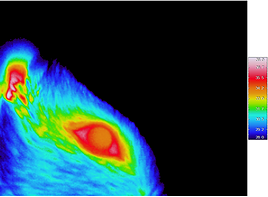

El investigador del Instituto de Neurociencias Félix Viana de la Iglesia lidera un proyecto para estudiar las bases moleculares de las sensaciones gélidas